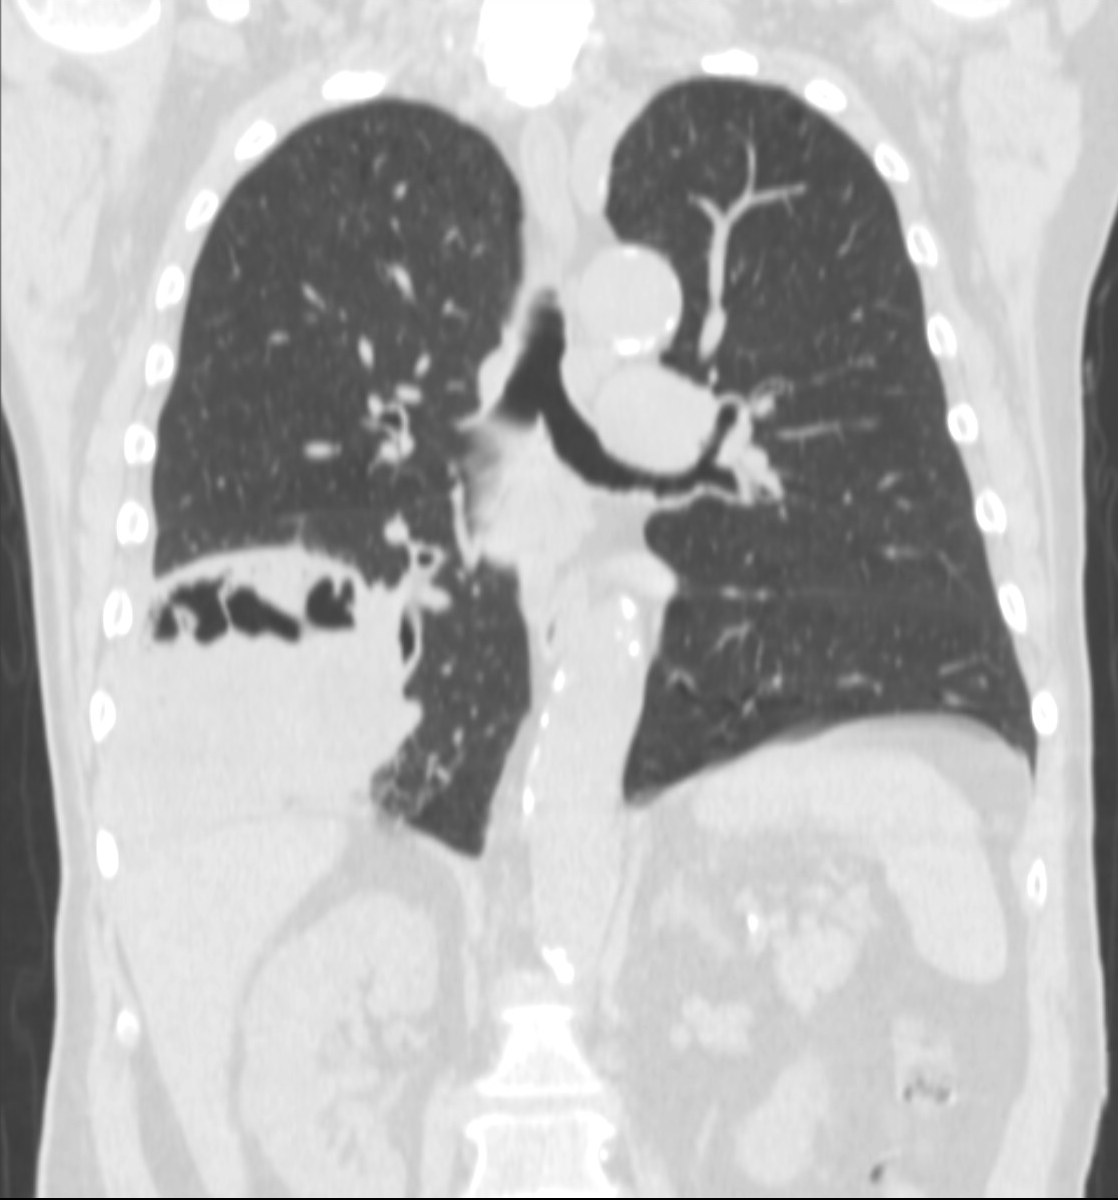

3a: Round shadow: multiple lung metastasis. Chest radiograph (PA)

3b: Multiple lung metastasis, CT lung window (axial, coronal reformat)

3c, coronal reformat

70 year old man, colon tumor.

Radiograph: Bilateral extensive, confluating patchy-nodular shadowing with diffuse reticular pattern. The diaphragm contour is partially blurry bilaterally: lymphangiosis carcinomatosa.

CT: Numerous 1-6 cm round and irregular, lobulated-spiculated contrast enhancing lesions in both lungs, everywhere sporadically.